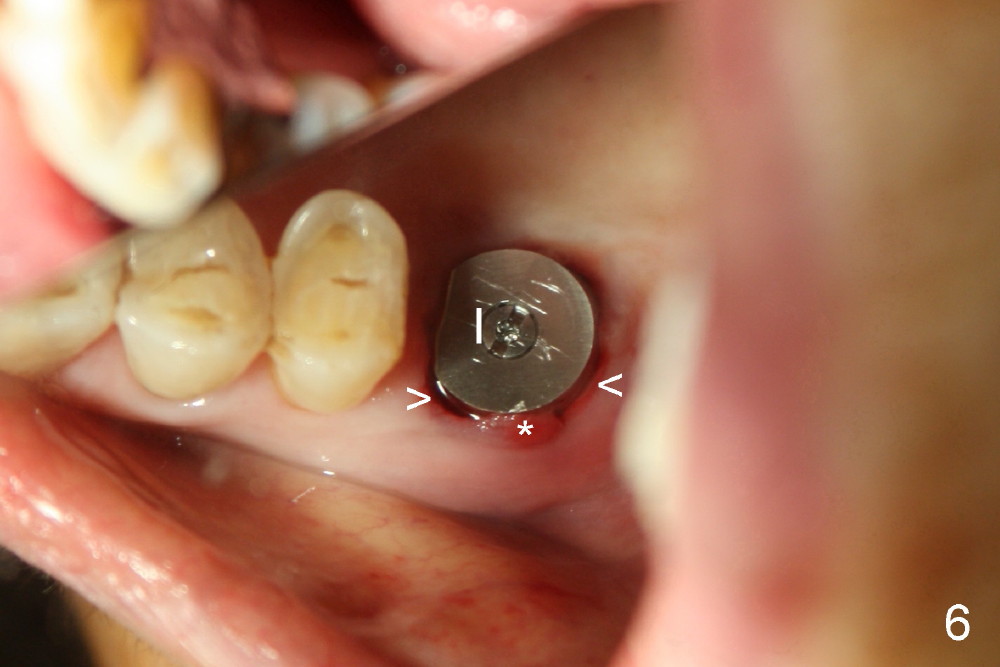

Extraction turns out to be simple with sectioning. After debridment of the socket and soaked with Clindamycin, the ostoeotomy forms using osteotomes, followed by insertion of a tap (Fig.4 T, 6x14 mm). After adjustment of the trajectory (Fig.4 arrow), larger taps are used (7x14, 8x14 mm) before placement of a 8x14 mm implant (Fig.5 I). There is small gap (Fig.6 arrowheads) around the implant. The wound is protected by perio dressing (Fig.7). The dressing is removed 7 days postop. Fig. 8 taken 2 weeks postop shows that the peri-implant gap has closed.